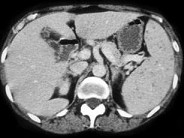

- 单项选择题骨髓移植患者发热,结合图像, 最可能的诊断为 ( )

A、脾念珠菌病

B、脾囊肿

C、肿瘤浸润脾

D、淋巴瘤

E、以上都不是